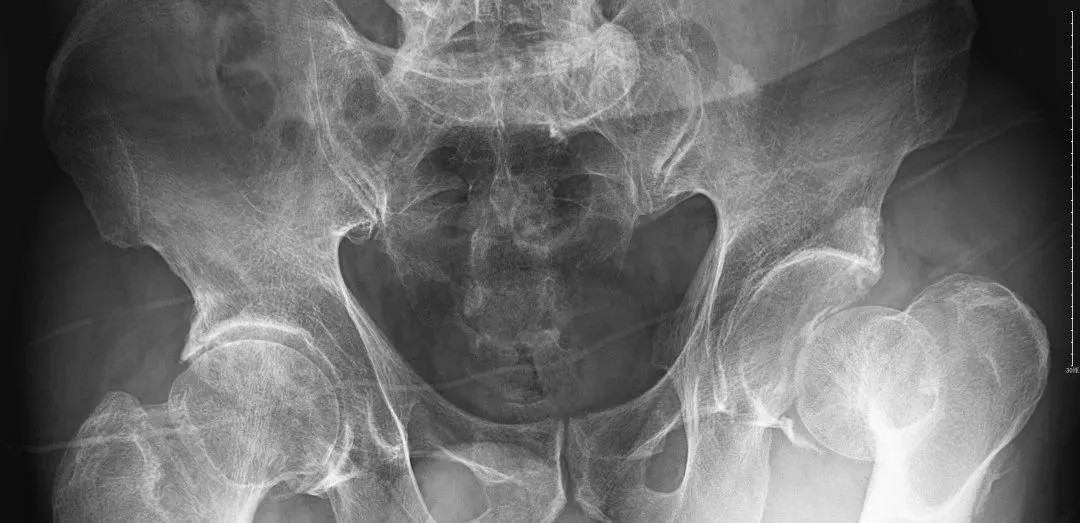

(術(shù)后復(fù)片  關(guān)節(jié)對(duì)位良好)